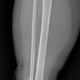

Saya cukup bingung dok untuk menentukan garis fraktur pada os tibia pasien, apakah ini termasuk fraktur inkomplit dok? Karena saya tidak melihat diskontinuitas tulang sejelas saya melihat diskontinuitas pada fibula

Alo dokter, fragmen tibia ada di distal melibatkan metafisis dan epifisis, ini termasuk fraktur intraartikuler

Alo dokter, setuju dengan pendapat dr.Yohannes Toban, saya melihat adanya garis fraktur pada bagian distal tibia daerah yang kita sebut dengan tibial plafond (pilon), dan medial maleolus nya. Baiknya supaya lebih jelas, boleh menambahkan rontgen Ankle joint.